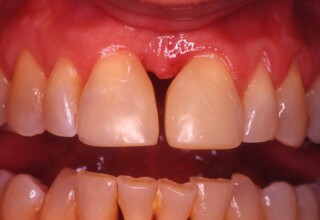

A rare case of dark root canal teeth with additional external absorption on the central incisor. After removal of the affected tissues of the central incisor, the tooth could not be directly bleached because of the soft tissue contact. The tooth was initially restored to provide the original tooth form, then it was bleached and the restoration was finalized.

Initial appearance

Final appearance